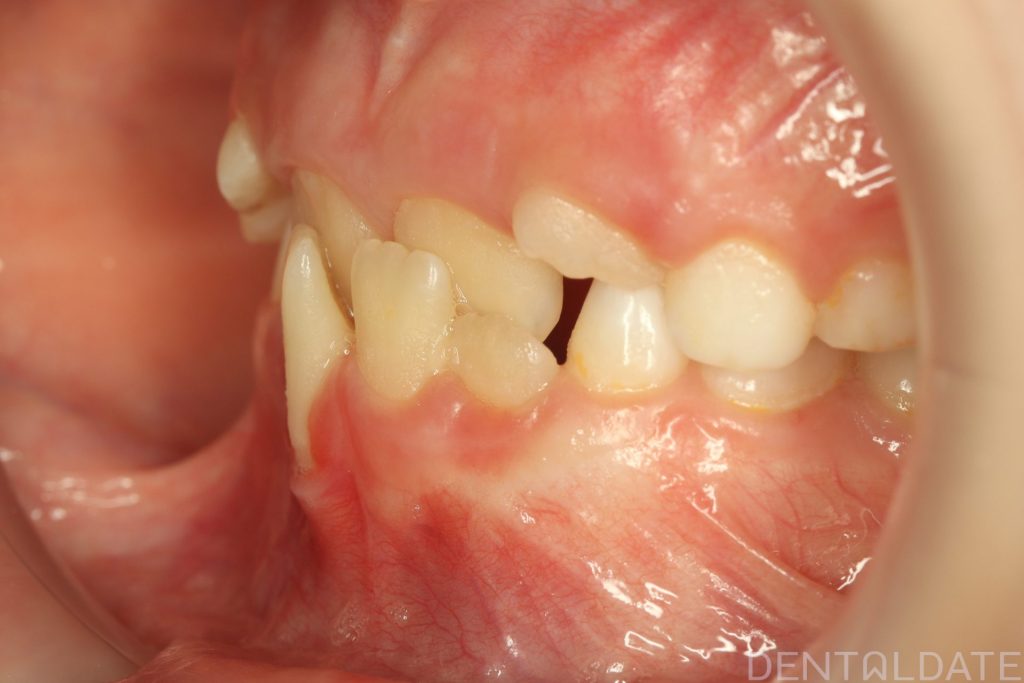

We are now focused on final adjustments to tooth alignment and occlusal height.